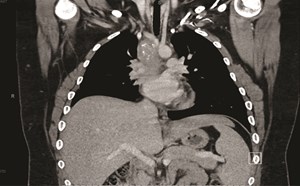

2nd Place Emage Winner: Fibrosing Mediastinitis